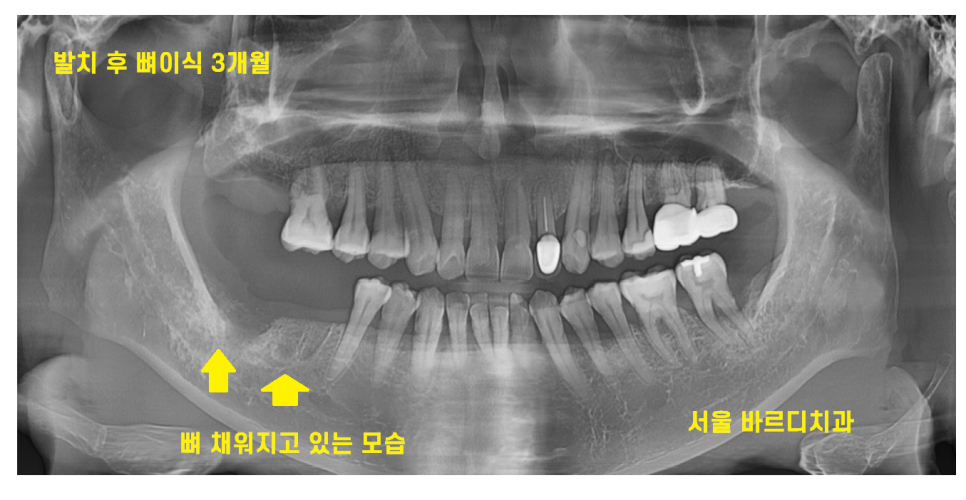

23.11.16

그로부터 또 한달이 지났습니다.

발치 후 뼈이식 3개월 정도 되었습니다.

아직도 웅덩이 진 모습이 보이긴 하지만..

그래도 전달에 비해서는 뼈가 만들어지고 있습니다.